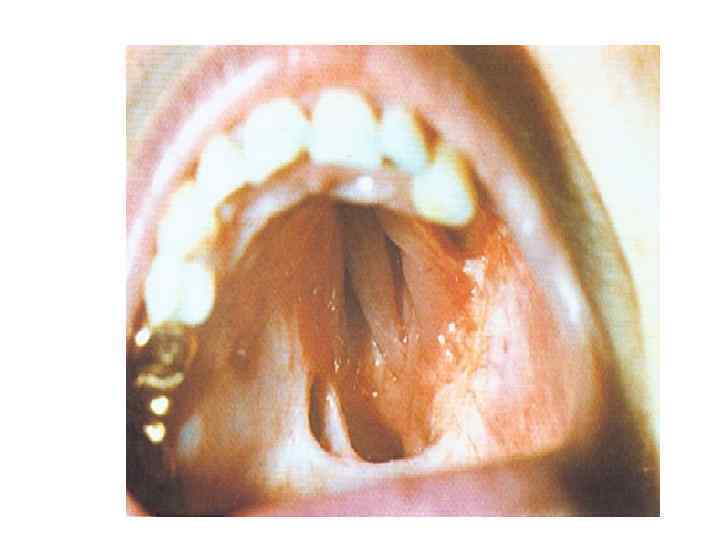

Третичный сифилис слизистых • Основные проявления – изолированные гуммы или гуммозная инфильтрация • Гуммы исходят из подлежащих костей и хрящей, реже – самих слизистых • Излюбленная локализация – область носа, мягкого и твердого неба, реже – язык, задняя стенка глотки, губы • Отсутствие лимфаденита • Быстрое разрешение под влиянием терапии (искл. – гуммозная инфильтрация языка)

Третичные поражения языка • могут проявляться в виде изолированных гумм или диффузного переходящего в рубец склероза (гуммозный глоссит, склеротический глоссит).

Третичные поражения твердого неба • Гуммозные и бугорковые • Ведут к перфорации твердого неба с образованием иногда весьма значительного дефекта. В результате полость рта сообщается с полостью носа, затрудняется прием пищи, так как она проникает из рта в полость носа, нарушается речь, появляется гнусавость. • Процесс может распространиться на носовую перегородку, разрушить её, вызвать деформацию носа. • При локализации процесса в области мягкого неба разрушению могут подвергнуться язычок и вся небная занавеска. • Заживление язвенной поверхности рубцеванием ведет к стойким и необратимым деформациям, причем особенно мучительной для больного является деформация твердого неба, что ведет к проблемам с приемом пищи и речи – гнусавость, поперхивание